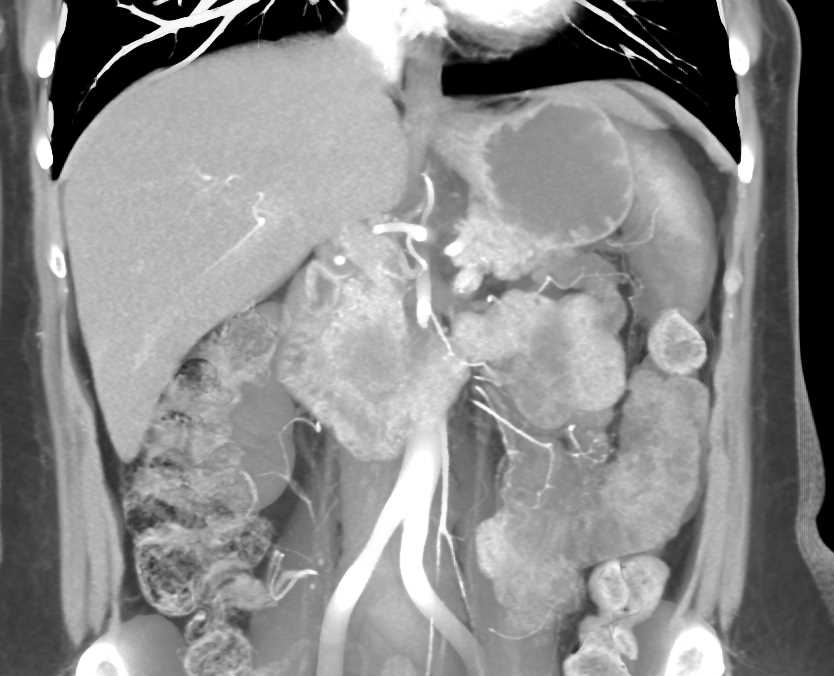

Adenocarcinoma of the Head of the Pancreas